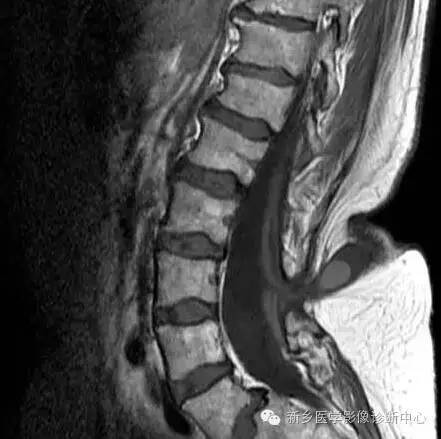

MR:

脊膜膨出:囊性肿块,与鞘膜囊想通;

脊髓脊膜膨出:囊性肿块内见脊髓或神经;

合并脊髓空洞,椎管脂肪瘤,脊髓低位,脊髓栓系,终丝粘连